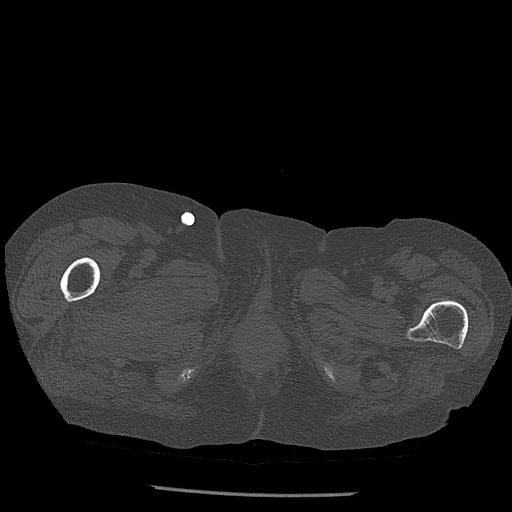

102803 1/12(キウスなし) 1/27 左下腿 4R 30歳女性 左脛骨軸内釘